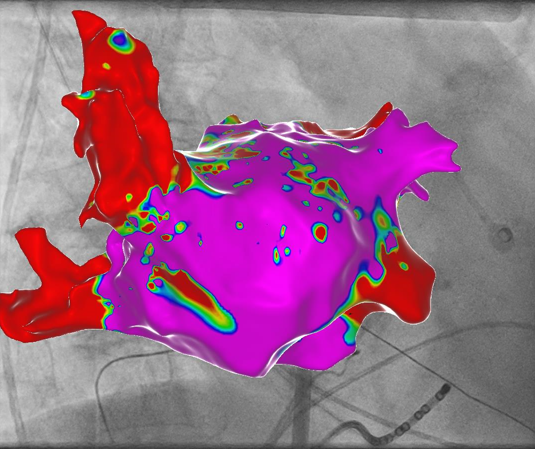

Vorhofflimmer Therapie - persönlich und individualisiert

Vorhofflimmern ist mit Abstand die häufigste Rhythmusstörung - jeder 3. Europäer wird im Laufe seines Lebens daran erkranken. Erfahren Sie mehr, wie wir Vorhofflimmern mit modernster Kathetertechnik behandeln - egal, ob Sie seit kurzem erkrankt sind, oder die Erkrankung bereits chronifiziert ist. Wir finden für Sie die richtige Technologie!

Links: Ultraschallbild eines Herzens, rechts: farbcodierte Substratkarte des Herzens